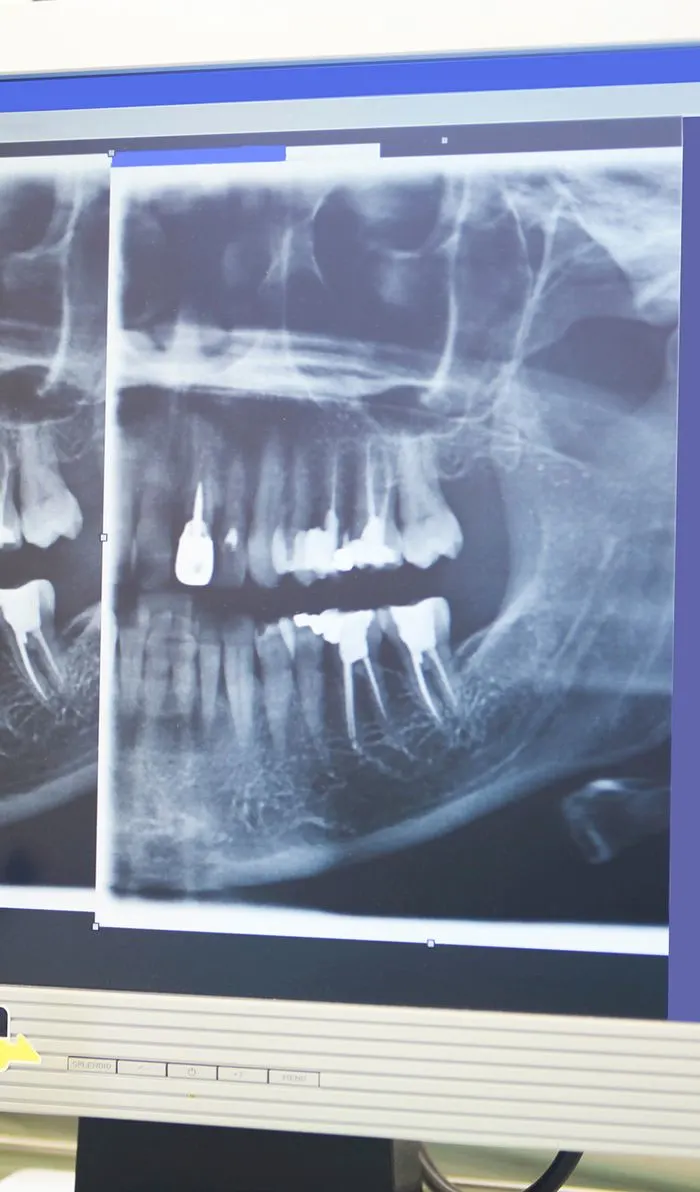

Digital Imaging

Advanced digital imaging techniques have taken the guesswork out of root canal therapy, resulting in a quicker, more efficient procedure with less pain and discomfort than ever before.